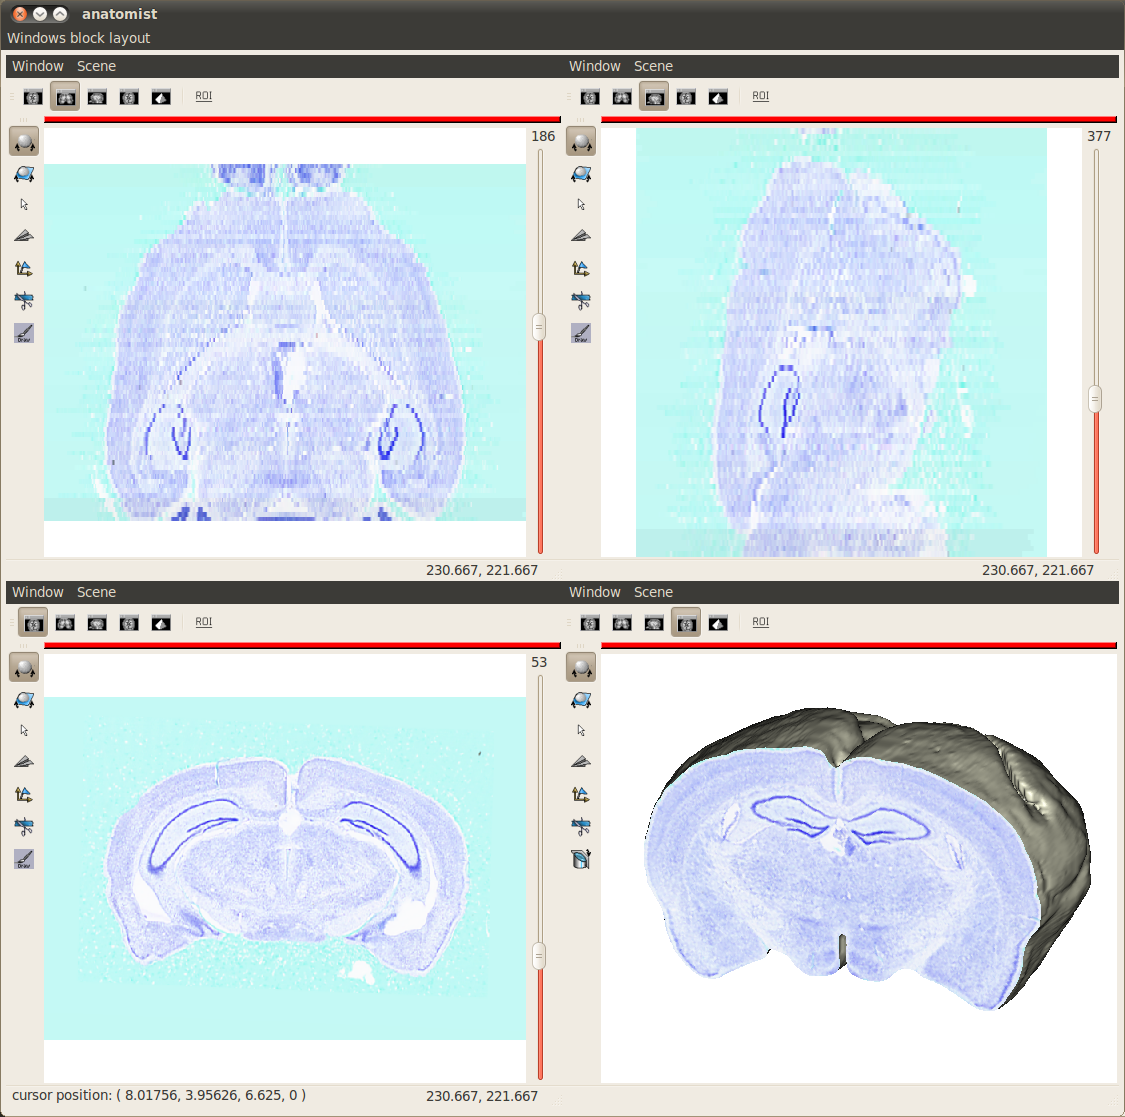

Anatomist | UNATI, CEA | all | all | Interactive 3D visualization |

BrainRAT toolbox | BioPICSEL, MIRCEN, CEA | 3.1 or > | all | Ex vivo 3D reconstruction and analysis |